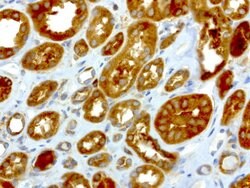

NME1 Mouse anti-Canine, Human, Rat, Clone: UMAB94, liquid, UltraMAB™

NME1 was identified because of its reduced mRNA transcript levels in highly metastatic cells. Nucleoside diphosphate kinase (NDK) exists as a hexamer composed of ′A′ (encoded by this gene) and ′B′ (encoded by NME2) isoforms. Mutations in the gene have been identified in aggressive neuroblastomas. Two transcript variants encoding different isoforms have been found for this gene. Co-transcription of this gene and the neighboring downstream gene (NME2) generates naturally-occurring transcripts (NME1-NME2), which encodes a fusion protein comprised of sequence sharing identity with each individual gene product.Specifications

| Immunocytochemistry, Immunofluorescence, Immunohistochemistry (Paraffin) | |